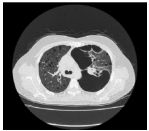

7.CC: cough for one year and back pain